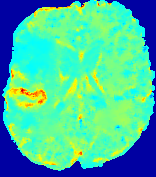

LesionRefer to captionRefer to captionRefer to captionRefer to captionRefer to captionRefer to caption𝐕rgbsubscript𝐕𝑟𝑔𝑏{\bf{V}}_{rgb}Refer to captionRefer to captionRefer to captionRefer to captionRefer to captionRefer to caption𝐕2subscriptnorm𝐕2{\|\bf{V}}\|_{2}Refer to captionRefer to captionRefer to captionRefer to captionRefer to captionRefer to captionRefer to caption3.53.53.52.82.82.82.12.12.11.41.41.40.70.70.70.00.00.0(mm/s)𝑚𝑚𝑠(mm/s)D𝐷DRefer to captionRefer to captionRefer to captionRefer to captionRefer to captionRefer to captionRefer to caption0.0200.0200.0200.0160.0160.0160.0120.0120.0120.0080.0080.0080.0040.0040.0040.0000.0000.000(mm2/s)𝑚superscript𝑚2𝑠(mm^{2}/s)Slice #1Slice #2Slice #3Slice #4Slice #5Slice #6

Figure 3: PIANO feature maps for one stroke patient, where the lesion is located in the left hemisphere. Top row: segmented stroke lesion region (white) on different slices, obtained from ISLES 2017. The corresponding slices for the PIANO feature maps are shown in the following rows.

For a better insight into an estimated velocity field 𝐕𝐕{\bf{V}} and diffusion field 𝐃𝐃{\bf{D}}, we compute the following maps: (1) 𝐕rgbsubscript𝐕𝑟𝑔𝑏{\bf{V}}_{rgb}: Color-coded orientation map of 𝐕=(Vx,Vy,Vz)T𝐕superscriptsuperscript𝑉𝑥superscript𝑉𝑦superscript𝑉𝑧𝑇{\bf{V}}=(V^{x},V^{y},V^{z})^{T}, obtained by normalizing 𝐕𝐕{\bf{V}} to unit length and mapping its 3 components to red, green, blue respectively; (2) 𝐕2subscriptnorm𝐕2\|{\bf{V}}\|_{2}: 222 norm of 𝐕𝐕{\bf{V}}; (3) D𝐷D: scalar field in Eq. 5.

Fig. 3 and Fig. 4 show the PIANO feature maps estimated from two ISLES 2017 patients: all are highly consistent with the lesion in both cases. Details of the blood flow trajectories are revealed in 𝐕rgbsubscript𝐕𝑟𝑔𝑏{\bf{V}}_{rgb} by the ridged patterns and the sharp changes of colors in the unaffected (right) hemisphere, while the flat patterns appearing within the lesion provide little directional information about the velocity and indicate low velocity magnitudes. Velocity magnitudes are more directly visualized via 𝐕2subscriptnorm𝐕2\|{\bf{V}}\|_{2}, from which one can easily locate the lesion where 𝐕2subscriptnorm𝐕2\|{\bf{V}}\|_{2} is low. D𝐷D also indicates lower diffusion values in the lesion, though with less contrast potentially due to the fact that it captures the accumulated effect of CA diffusion at the voxel-level.